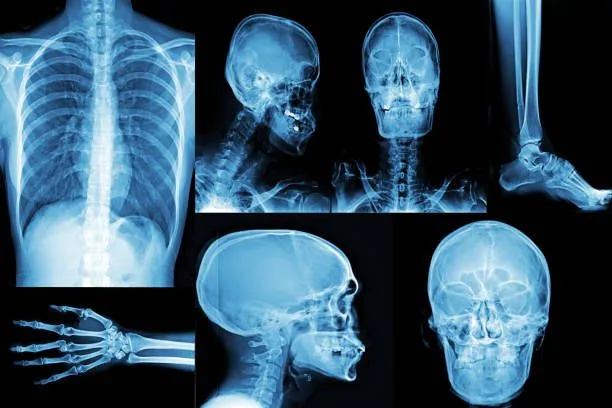

<>X-rays are a vital diagnostic tool that allow doctors to view bones, joints, and some soft tissues. According to RadiologyInfo.org, X-rays are most commonly used to detect fractures, infections, and arthritis, but they can also help identify lung issues like pneumonia.Urgent care clinics use X-rays to:

How X-Rays Work

X-ray machines pass small doses of radiation through the body to create an image. Dense materials like bone show up as white, while softer tissues appear darker. According to the Mayo Clinic , the process is quick, painless, and typically completed within a few minutes.